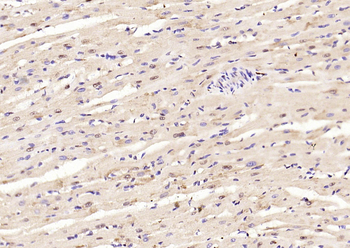

Phospho-Smad3 (Ser423 + Ser425) Rabbit Polyclonal Antibody [orb6983]

FC, IF, IHC-Fr, IHC-P, WB

Bovine, Canine, Equine, Gallus

Human, Mouse, Porcine, Rat

Rabbit

Polyclonal

Unconjugated

100 μl, 200 μl, 50 μlPhospho-SMAD5 (Ser463 + Ser465) Recombinant Rabbit Monoclonal Antibody [orb559123]